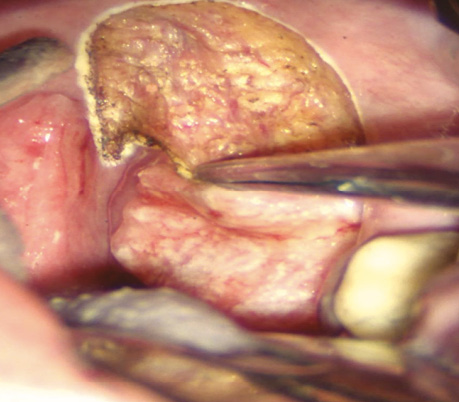

Пацієнт С., 56 років. Діагностовано плоскоклітинну карциному передньої піднебінної дужки з поширенням на корінь язика T2N0M0. Проведено трансоральну CO₂-лазерну резекцію бічної стінки ротоглотки та кореня язика доступом через сформоване «вікно» в ділянці дна ротової порожнини. На рис. 3–6 наведено етапи хірургічного втручання.

Рис. 3. Виконано розріз по серединній лінії дна ротової порожнини між під’язиковим мʼясцем у сагітальній площині

Рис. 4. Дисекція в напрямку до підпідборідного простору між черевцями підборідно-язикового та підборідно-під’язикового м’язів через щелепно-під’язиковий м’яз і між передніми черевцями двочеревцевого м’яза. Накладено лігатуру на кінчик язика, язик виведено через сформоване «вікно» дна ротової порожнини, що забезпечило візуалізацію кореня язика в анфас